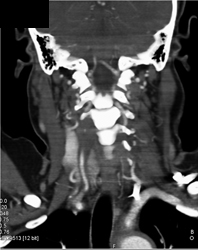

Trauma to Carotid Artery With Bleed